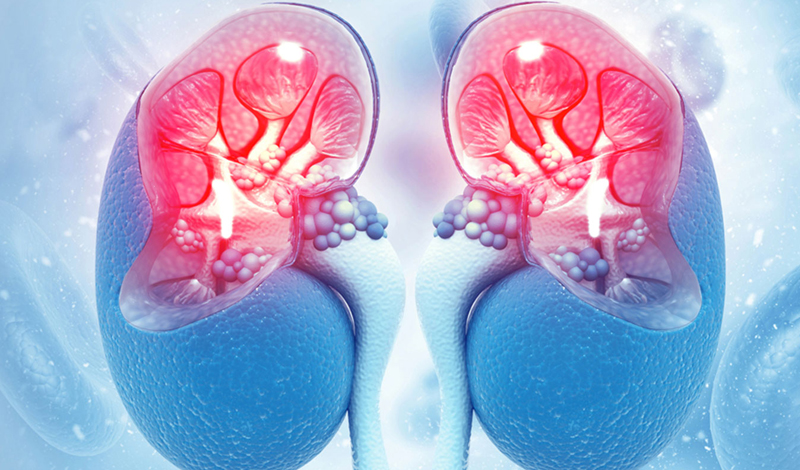

Specialized Nephrology Services

Diabetic Kidney Disease

Diabetic Kidney Disease, also known as diabetic nephropathy, is a common and serious complication

Hypertensive Kidney Disease

Hypertensive Kidney Disease is a condition in which long-standing high blood pressure gradually